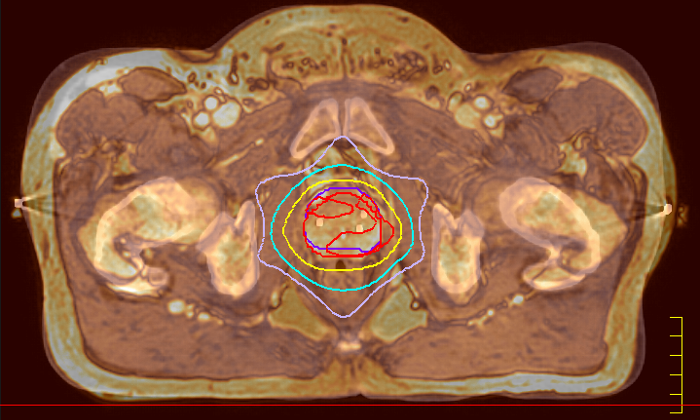

With its exceptional soft-tissue visualization capabilities and wide range of image contrasts, MRI has become a powerful tool to help more precisely define tumor boundaries. This is particularly important as it has been established that there is a high degree of uncertainty in target volume delineation, and it is even reported to represent the largest uncertainty in the entire radiotherapy process for most tumor sites**. Better visualization of the target area and nearby organs-at-risk is a key factor in enhancing target volume delineation. MRI’s expanding role also can be attributed to its functional imaging capabilities, which can inform both target characterization and treatment response.

Ingenia MR-RT is a dedicated MR simulation platform that provides high quality, high contrast MR images acquired with the patient in treatment position. Designed for the needs of radiation oncology, this comprehensive solution provides the tools and software needed for versatile and efficient imaging for radiotherapy planning.